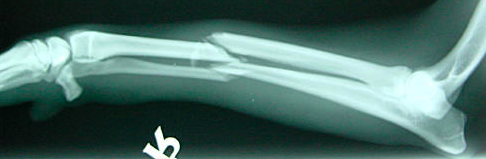

Pasienten har tatt seg for ved fall. Nå hevelse, smerte og feilstilling i underarm. Diagnose?

Antebrakiumfraktur.

Etter operasjon - fritt bevegelig, men ikke belastning de første 8 ukene.

Hva er en såkalt Galeazzifraktur?

Brudd i radiusskaftet( oftest mellom midtre og distale 1/3) og samtidig dislokasjon av distale radioulnarleddet(DRUJ). Skyldes oftest fall eller traume.